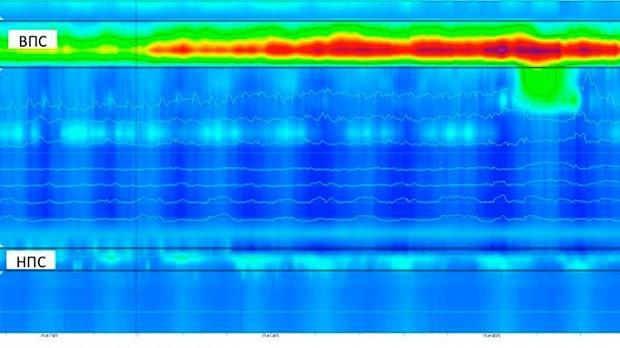

Основные положения. Гастроэзофагеальная рефлюксная болезнь - патогенетически неоднородное заболевание, которое зачастую обусловлено нарушениями двигательной функции грудного отдела пищевода и нижнего пищеводного сфинктера, приводящими к длительной экспозиции агрессивного кислого и щелочного содержимого желудка и двенадцатиперстной кишки в пищеводе. Применение многоканальной внутриполостной рН-импедансометрии и манометрии пищевода высокого разрешения позволяет с высокой точностью установить основополагающие патогенетические механизмы развития гастроэзофагеальной рефлюксной болезни у конкретного больного, идентифицировать характер рефлюктата, подобрать оптимальную схему терапии, избежать хирургического лечения.

Ключевые слова: гастроэзофагеальная рефлюксная болезнь, внутриполостная рН-импедансометрия пищевода, манометрия пищевода высокого разрешения